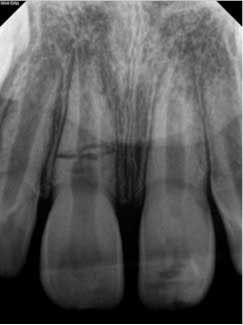

At approximately one year, the patient returned for follow-up. Clinical testing was equivalent to earlier recall visits. Radiographically, the tooth showed continued apical development with further development of a calcific barrier at the fracture line (figure 4). Furthermore, the medial aspect of the fractures showed repair.